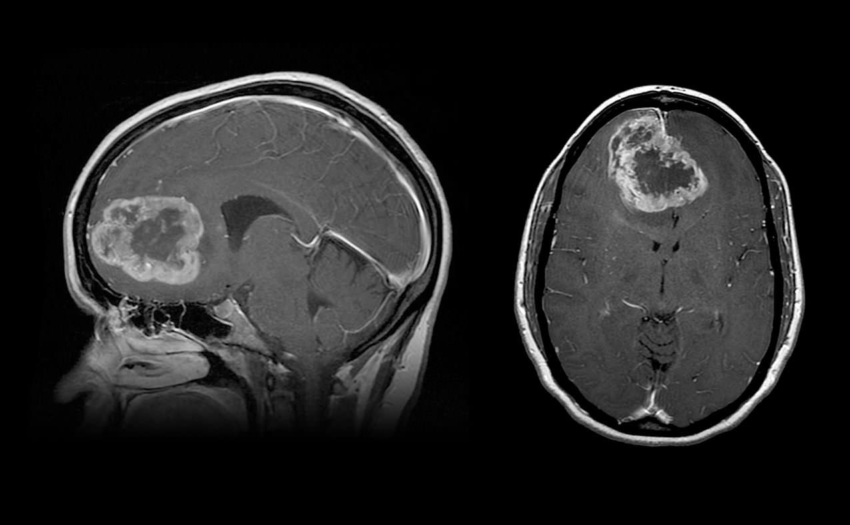

Tumeur au cerveau Photo Stock Alamy. j'ai en 1997 été opéré d'une tumeur de 45mm au cerveau, on l'appelle macroadenome hypophisaire expansif a prolactine, on me l'a irradié et ce n'est selon mon specialiste que ne peut plus voir, pas guérri. Medisite vous explique comment les identifier avec l'expertise du Dr Julien Geffrelot,.